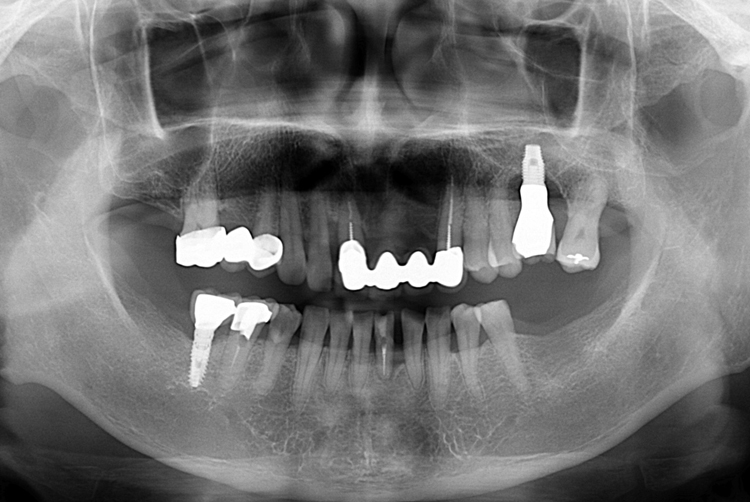

[임플란트] 어금니 임플란트

치료전 : 2018-03-20